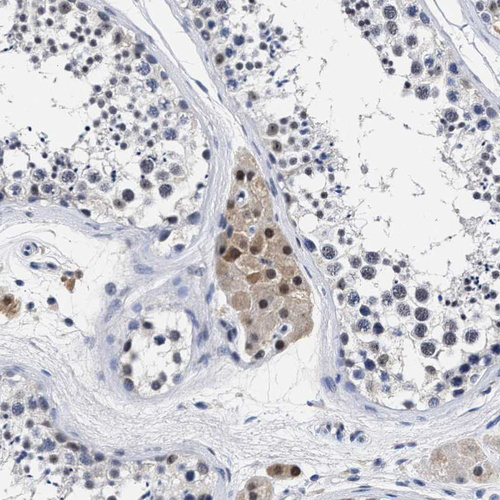

Immunohistochemical staining of human urinary bladder shows strong nuclear and cytoplasmic positivity in urothelial cells.